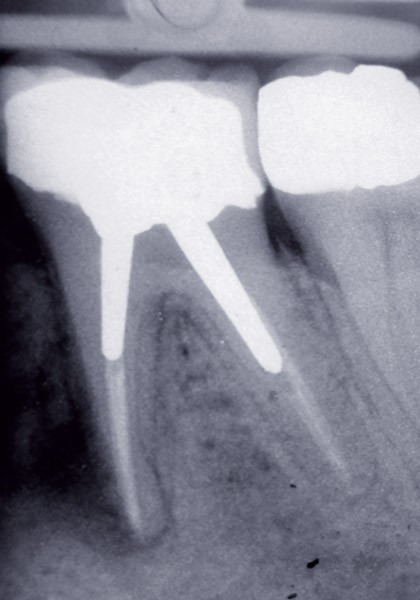

Le pilier prothétique est indispensable à la prothèse fixée. Sa pérennité dans le temps est un critère majeur dans la prise de décision entre un traitement conservateur ou implantaire unitaire.

Dans un environnement parodontal sain, la chronologie des traitements conservateurs suite à la pathologie carieuse serait la suivante : le traitement endodontique de première intention, le retraitement endodontique et la chirurgie endodontique, voire l’amputation radiculaire. En cas d’échec, l’alternative implantaire pourra être envisagée (fig. 1).